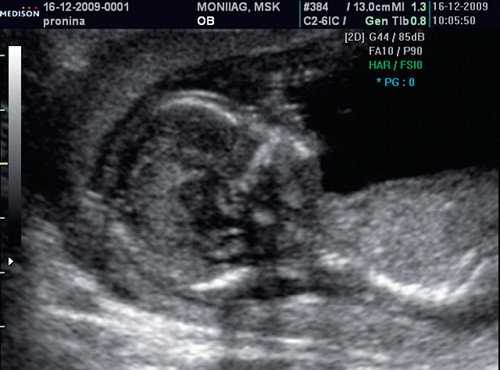

Копчико-теменной размер плода (КТР) для проведения скрининга I триместра должен быть в пределах 45-84 мм. Для оценки носовой кости в I триместре беременности необходимо соблюдать строгие условия. Это адекватное увеличение (на снимке должны быть только голова и верхняя часть грудной клетки), среднесагиттальный скан (должны быть визуализированы эхогенный кончик носа, небный отросток верхней челюсти, диэнцефалон), нос представлен тремя "К" (кончик носа, кожа, кость). Кожные покровы и кости носа визуализируются в виде знака "равенства", нос параллелен датчику.

Если все критерии соблюдены, то на уровне носа плода должны быть видны три четко различимые линии: верхняя линия представляет собой кожу, книзу от нее визуализируется более толстая и более эхогенная, чем кожа носовая кость. Третья линия, визуализируемая кпереди от носовой кости и на более высоком уровне, чем кожа - это кончик носа (рис. 1).

Рис. 1. Нормальная носовая кость.

Считается, что носовая кость нормальна, когда она по своей структуре более эхогенна, чем надлежащая кожа и патологична, если она не видна (аплазия) (рис. 2) или ее длина меньше нормы (гипоплазия) (рис. 3). В случае одинаковой или меньшей эхогенности носовой кости чем кожи носовая кость считается патологической (рис. 4).

а) Носовая кость в 12 нед и 2 дня длиной 1,4 мм (меньше нижней границы нормы).

б) Носовая кость 2,1 мм в 14 нед у плода с синдромом Дауна.